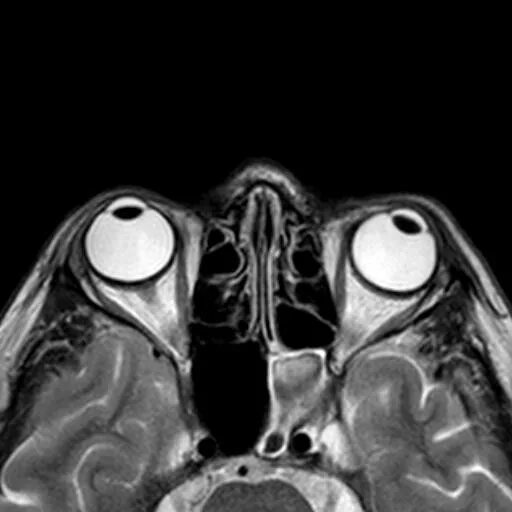

Мрт орбит и зрительных нервов